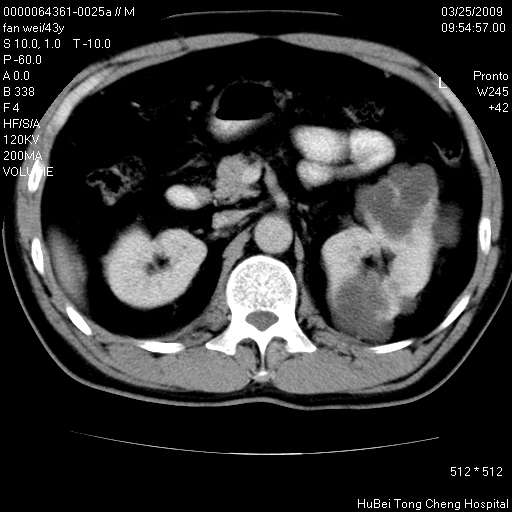

患者 男,43岁。左侧腰部不适两天。平素健康。无家族遗传病史。

腹部彩超提示:1)轻度脂肪肝。2)左肾多发囊性占位性病变;建议行进一步检查。

临床诊断:左肾多发囊性占位性病变,性质待定(多发肾囊肿?)。

双肾ct轴位平扫+增强扫描(层厚10mm,螺距1.0,重建间隔10mm),图像如下:

多囊肾的影像诊断标准:有阳性家族史,年龄<30岁,单侧或双侧肾脏有两个肾囊肿;30~59岁,两侧肾脏各有两个肾囊肿;60岁以上,每侧肾脏有4个囊肿。敏感性和特异性达86%和80%。

此病例影像诊断符合,要结合家族史,腰痛、血尿、尿路感染史,有无高血压等综合判断,如无相应的临床症状,本身病变也无意义了(个人观点)

双肾多发性囊肿

双侧多囊肾!

双肾多发性囊肿   脂肪肝